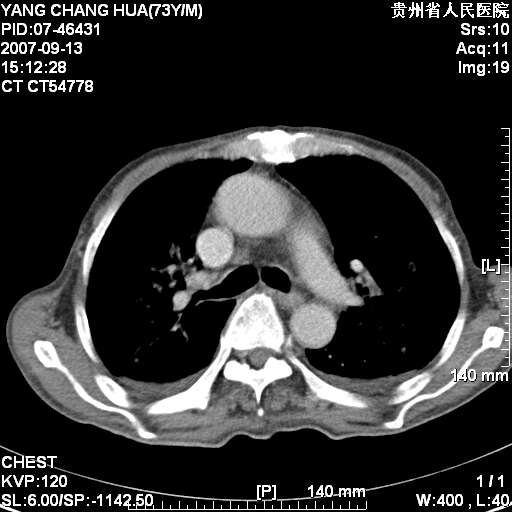

标题: CT9726:M73Y,患者因吞咽困难及腹痛半月入院!全身浅表淋巴结 [打印本页]

图像没有传全。肺部为感染性病灶;肺囊肿;双侧胸腔积液;肝脾肿大;腹水。

双肺部为感染性病灶.双侧胸腔积液;肝脾肿大;腹水.

双肺部为感染性病灶.双侧胸腔积液;肝脾肿大;脾脏密度不均,不除外脾侵润?腹水.

双肺点片状影,以双上肺改变明显.双侧胸腔积液.为感染性病灶,但不除外结核.

双肺散在斑片状及多发小结节状阴影,边缘模糊,双上肺野明显,双侧胸膜腔少量积液,纵隔及肺门区未见明显肿大淋巴结,肝脾肿大,脾内见多发低密度区,结合临床考虑恶性淋巴瘤(肺内表现为肺炎肺泡型),单看影像表现,肺结核不能排除。建议结合实验室检查或表浅淋巴结活检。